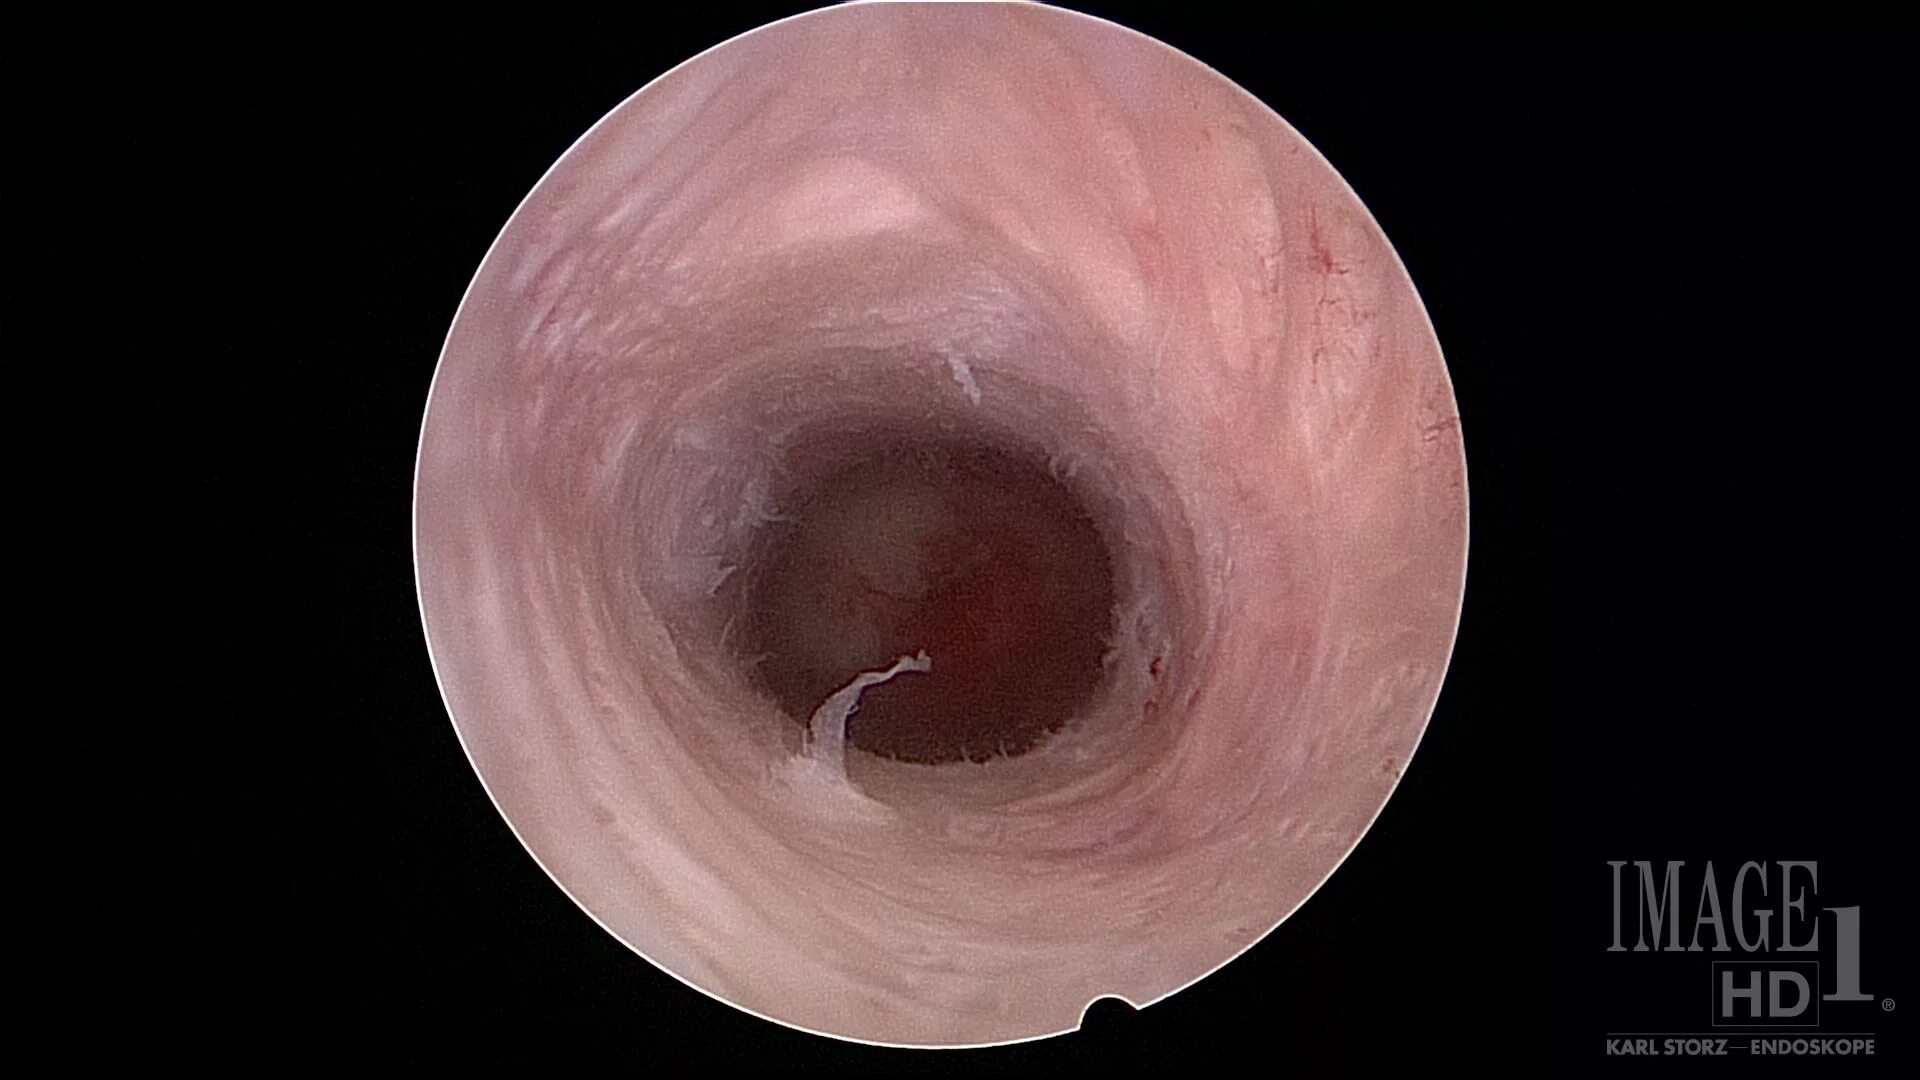

Цервикоз шейки матки